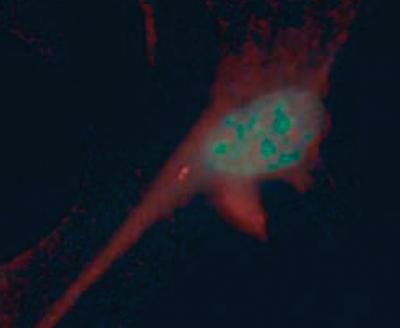

Norimasa Mitsuma, Ph.D., a postdoctoral student in Katsanis’s lab, also demonstrated that the defective cilia weren’t hindering brain function. He repeatedly dunked one hind paw in hot water for an hour and then carefully measured nerve activity at the base of the spinal cord - the junction between leg and brain. While regular mice displayed clear spinal nerve activity, Bbs- mice did not. This highlighted that the problem with Bbs- mice is that sensory information cannot reach the brain.